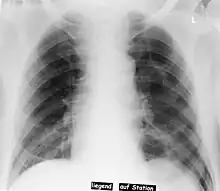

Neumotórax a la izquierda

En radiología, el Signo del surco profundo en una radiografía de tórax supina es un indicador indirecto de neumotórax.[1][2]

En una radiografía supina, este signo se ve como un luminoso y profundo ángulo costofrénico ipsilateral,[3] dentro de las porciones no dependientes del espacio pleural en oposición al ápice (del pulmón) cuando el paciente está en posición vertical. El ángulo costofrénico es anormalmente profundo cuando el aire pleural se acumula lateralmente, produciendo el signo del surco profundo.[4]

Los pacientes con enfermedad pulmonar obstructiva crónica (EPOC) pueden mostrar ángulos costofrénicos profundos laterales debido a una hiperaireación de los pulmones y provocar un falso positivo para este signo.